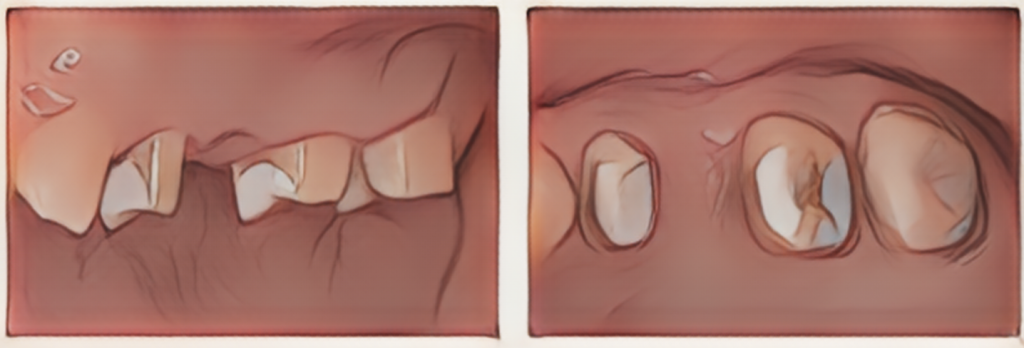

患者様は奥歯を1本失われ、治療方針を含めた相談のために来院されました。歯の欠損部位とその周りの歯の状況を調べていくと、残った歯の部分にも複数の虫歯があることが確認できました。

銀の詰め物を外したところ、広範囲の虫歯のため、かぶせ治療が必要な状況でした。

土台の歯の虫歯を除去したところ、神経を残した状態でブリッジ修復ができると判断できました。